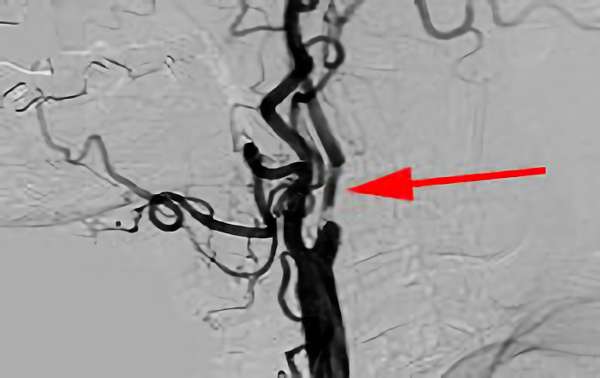

アテローム血栓性 脳梗塞

手術前1

手術前2

手術中1

手術中2

手術後1

手術後2